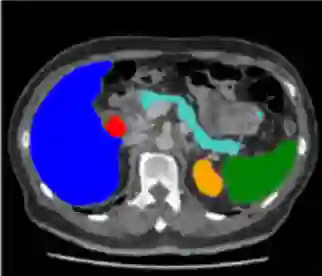

Medical image segmentation remains particularly challenging for complex and low-contrast anatomical structures. In this paper, we introduce the U-Transformer network, which combines a U-shaped architecture for image segmentation with self- and cross-attention from Transformers. U-Transformer overcomes the inability of U-Nets to model long-range contextual interactions and spatial dependencies, which are arguably crucial for accurate segmentation in challenging contexts. To this end, attention mechanisms are incorporated at two main levels: a self-attention module leverages global interactions between encoder features, while cross-attention in the skip connections allows a fine spatial recovery in the U-Net decoder by filtering out non-semantic features. Experiments on two abdominal CT-image datasets show the large performance gain brought out by U-Transformer compared to U-Net and local Attention U-Nets. We also highlight the importance of using both self- and cross-attention, and the nice interpretability features brought out by U-Transformer.